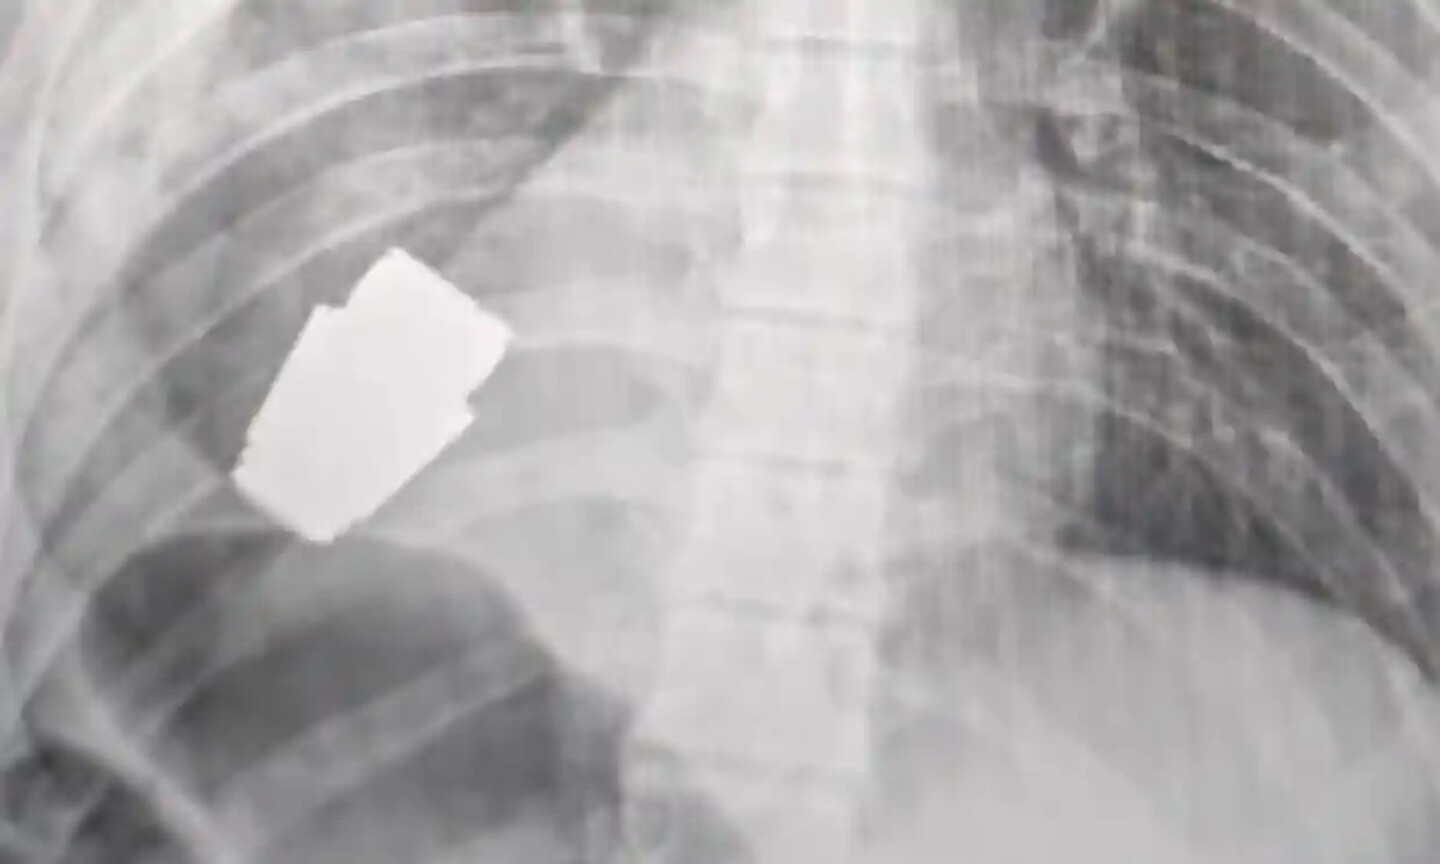

Los cirujanos extrajeron el arma que se encontraba justo debajo del corazón del soldado herido, mientras que dos zapadores se encargaron de que la operación se llevara a cabo de forma segura, indicó Hanna Maliar, viceministra de Defensa de Ucrania, que publicó una imagen en la que aparentemente se ve una radiografía del artefacto dentro del cuerpo del soldado.

“Médicos militares realizaron una operación para extraer una granada VOG, que no estalló, del cuerpo del soldado”, escribió en una publicación de Facebook.

La operación se realizó sin emplear la electrocoagulación —un método habitual para controlar las hemorragias durante la cirugía— debido a que “la granada podía detonar en cualquier momento”, indicó Maliar.

Gerashchenko escribió en una actualización de Telegram a primera hora del jueves: “La parte no detonada de la granada fue extraída de debajo del corazón. La granada no explotó, pero siguió siendo explosiva”.